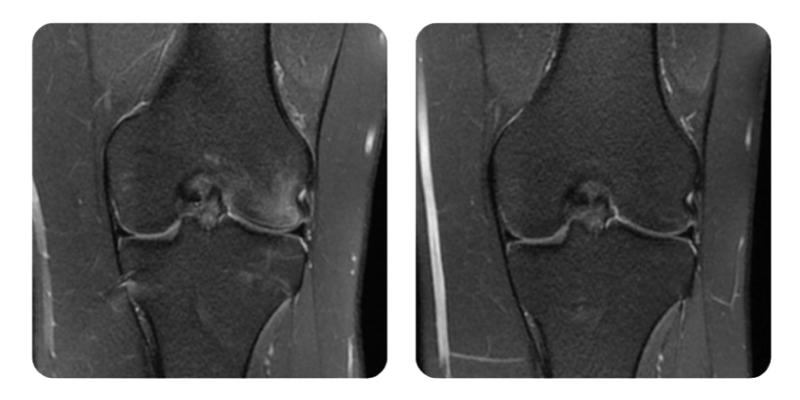

Prima

Dopo

M.A., 21 anni - Osteonecrosi del condilo femorale esterno sinistro

Diagnosi: Osteonecrosi del condilo femorale esterno sinistro, grado I.

Interventi terapeutici: Ossigenoterapia iperbarica secondo protocollo: 20 sedute, seguite da valutazione RMN a fine ciclo.

Rivalutazione: Gli esami di imaging confermano la guarigione completa, con remissione totale dell'edema (100%). Il ginocchio sinistro presenta mobilita quasi normale, senza dolore.